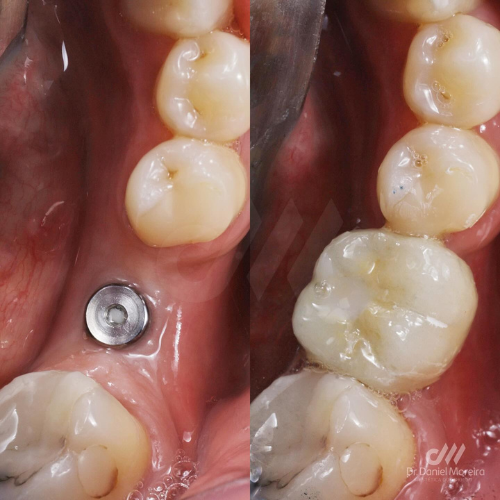

O implante dentário é uma estrutura de титânio (material altamente biocompatível) instalada no osso da mandíbula ou maxila, que funciona como a raiz de um dente perdido.

Após a cicatrização, é colocada uma prótese sobre esse implante, resultando em um dente com aparência e função muito próximas ao natural.

O implante é instalado no osso com anestesia local, de forma segura e minimamente invasiva.

4. Cicatrização (osseointegração)

O implante se integra ao osso, garantindo estabilidade. Esse processo pode levar alguns meses.

5. Colocação da prótese

É feita a instalação do “novo dente”, devolvendo estética e função.